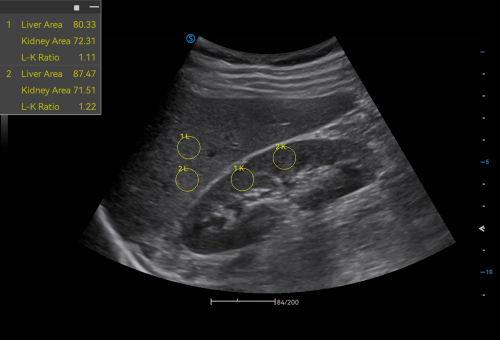

· HRI QA assesses hepatic steatosis by quantitative results with multiple sampling points available.